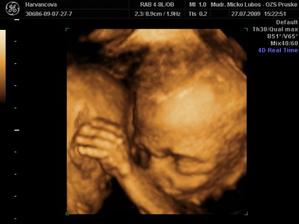

Ďalšie bábätko sme plánovali v roku 2009. Aj sa podarilo. 30.3.2009 pozitivny test... K lekárovi som sa neponáhľala, veď čo ma môže prekvapiť... A predsa... 4.5.2009 na prvej kontrole v 10tt sa ukázalo, že čakáme dvojičky... 🙂)) Spočiatku to bol šok, ale celkom sme sa s tym vysporiadali a snažíme sa prispôsobiť novej situácii...